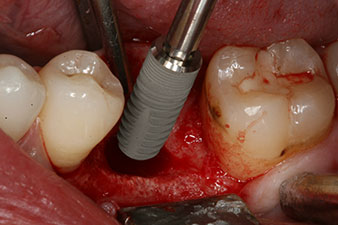

Шест седмици след екстракцията се открива непълна осификация след препарацията на мукопериосталното ламбо в областта на предходната алвеола мезиално.

Имплантът е поставен както е планирано след цялостно отстраняване на гранулационната тъкан (blueSky, bredent).

Въртящият момент, използван за машинно-задвижвано поставяне, е 43 Ncm. Освен това, след завинтване на измервателния щифт (SmartPeg), специално пригоден за импланта, стойността на ISQ се измерва със сондата на W&H Osstell ISQ модула.